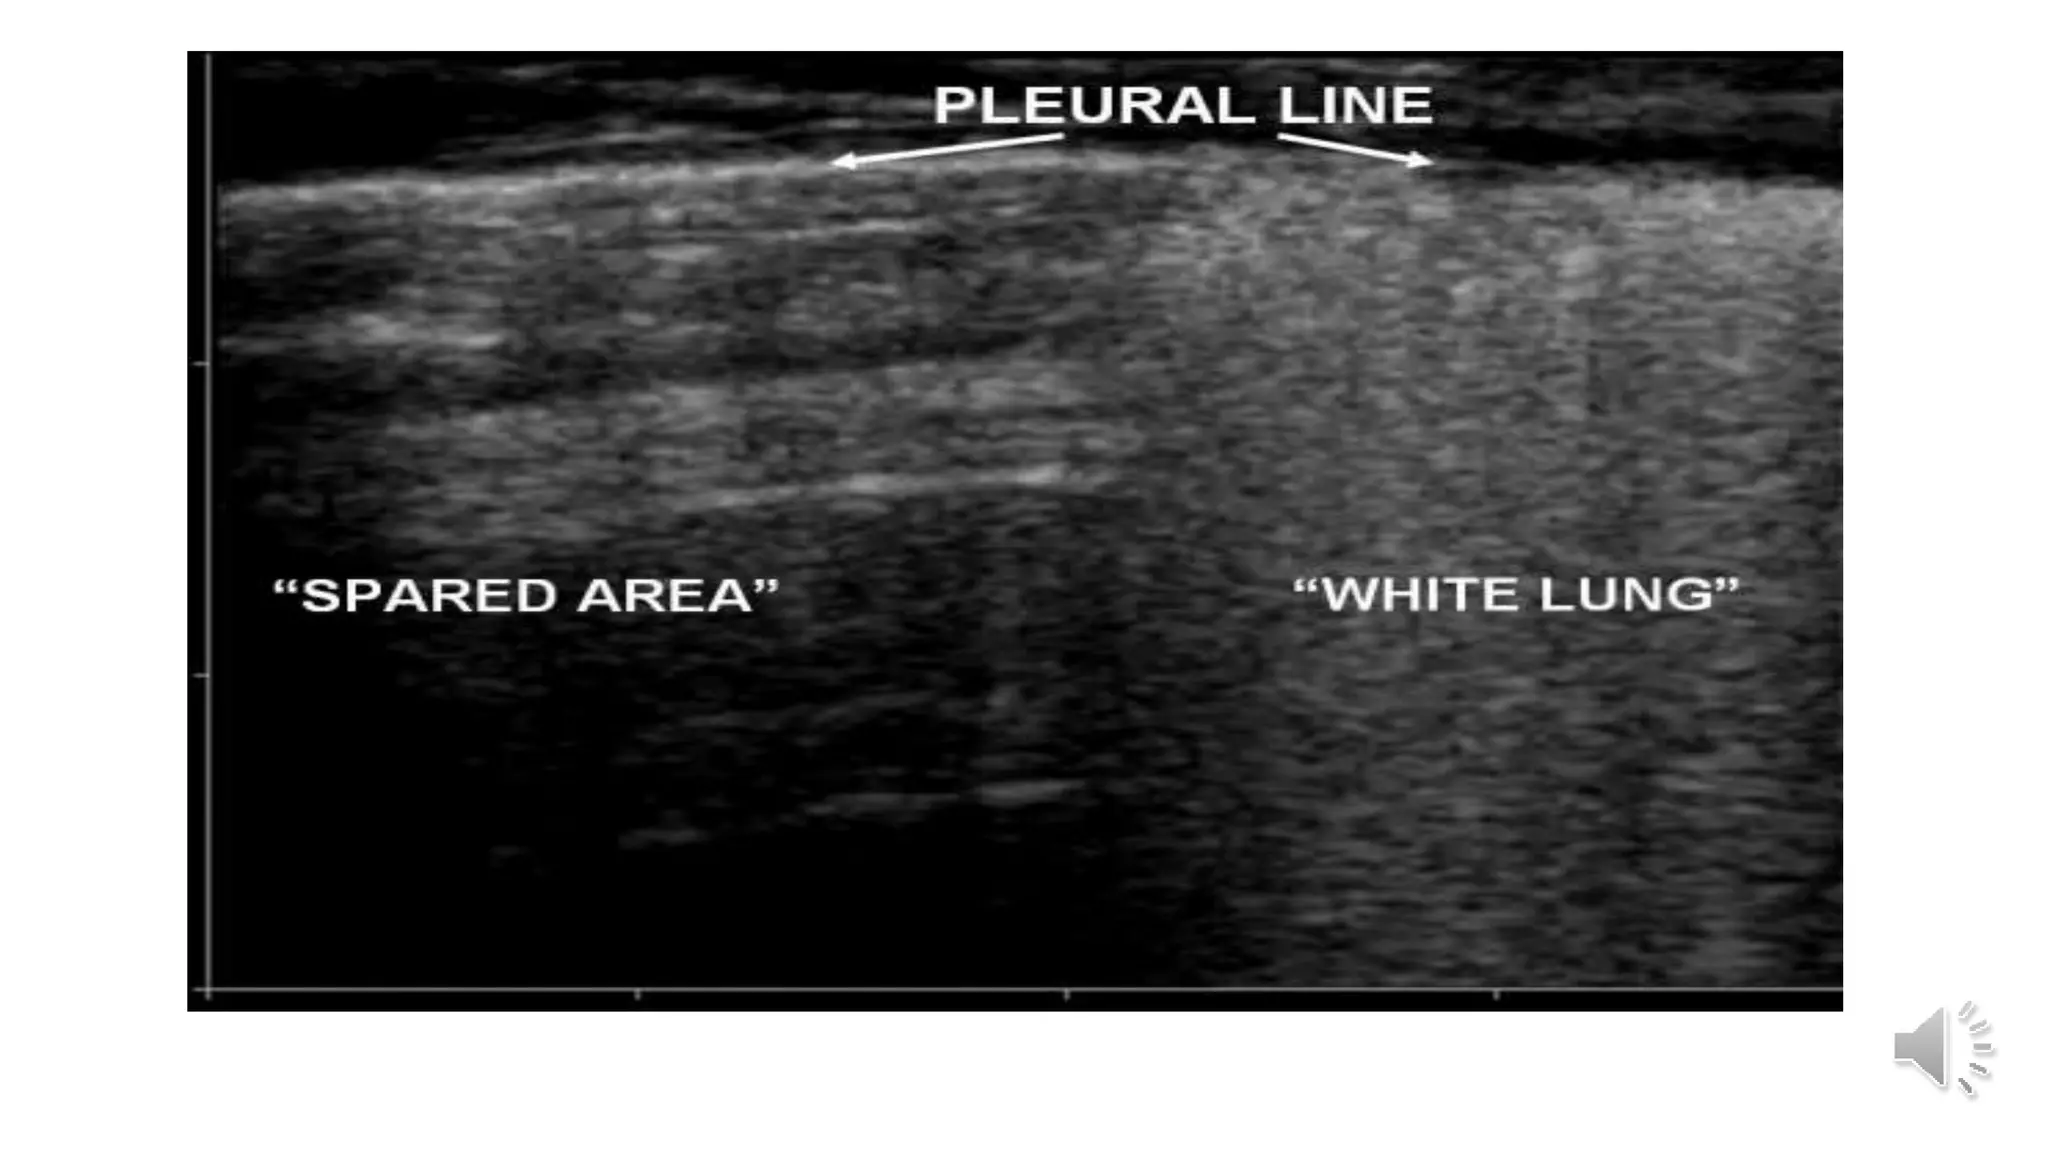

Table 5 CT and ultrasonographic features of COVID-19 pneumonia

Thickened pleura Thickened pleural line

Ground glass shadow and effusion B lines (multifocal, discrete, or confluent)

Pulmonary infiltrating shadow Confluent B lines

Subpleural consolidation Small (centomeric) consolidations)

Translobar consolidation Both non-translobar and translobar consolidation

No Pleural effusion No Pleural effusion

More than two lobes affected Multilobar distribution of abnormalities

Negative or atypical in lung CT images in

the super-early stage, then diffuse

scattered or ground glass shadow with

the progress of the disease, further lung

consolidation

Focal B lines is the main feature in the early stage and in

mild infection; alveolar interstitial syndrome is the main

feature in the progressive stage and in critically ill

patients; A lines can be found in the convalescence;

pleural line thickening with uneven B lines can be seen in

patients with pulmonary fibrosis